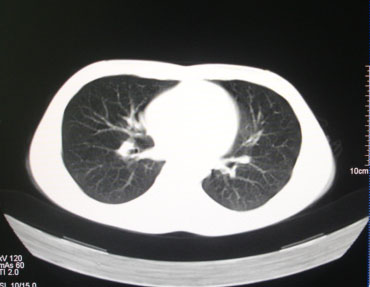

标题: CT26938:单发肺窗

病人17岁。咳嗽伴血丝痰2年?外院x片示左上肺椭圆形影,疑胸腺瘤

左肺尖见占位,建议上传纵隔窗及向上扫描。

左上纵隔占位性病变?